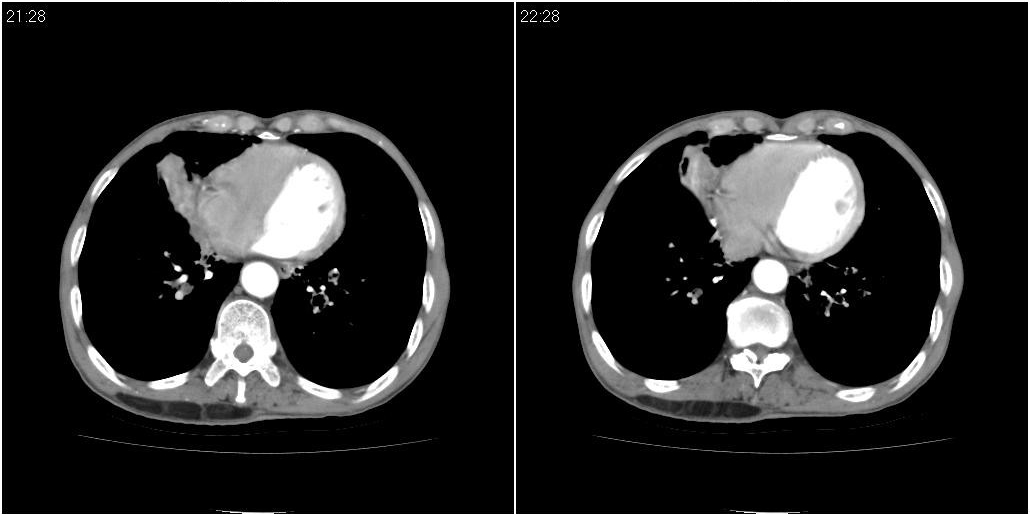

标题: CT25416:男性,70岁。胸片发现右下肺斑片状阴影

以下是ct检查的情况:

标题: ct增强: